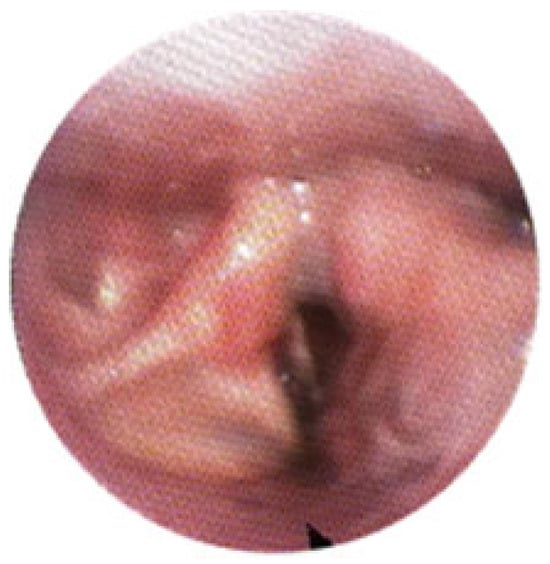

- A diagnosis of a venous malformation confirmed by radiological imaging (magnetic resonance imaging (MRI), CT, or ultrasound) and/or direct endoscopic visualization.

- Location of the venous malformation (VM) within the airway, including the soft palate, tongue, oropharynx, or subglottic space.

3.1. Magnetic Resonance Imaging (MRI) Findings

3.2. Clinical Outcomes